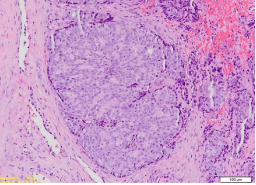

Pathology examination of the haematoxylin and eosin (H&E) slides of his biopsied lesion demonstrated tumour islands that consisted of central cells with hypo-chromatic and vacuolated nuclei, pale eosinophilic cytoplasm, and this had exhibited pleomorphism. The peripheral basal tumour cells were found upon pathology examination to be spindle-shaped and appeared hyperchromatic (see Figure 3), with areas of extensive comedonecrosis visualised. The central tumour cells had exhibited immunohistochemistry staining positivity for PSA (see Figure 4A) and cytokeratin (CK; weak). The peripheral basal tumour cells were noted to have exhibited immunohistochemistry staining positivity for PSA, CK (weak), and p63 (scattered) (see Figure 4B). Both the central tumour cells and the basal tumour cells had exhibited negative staining for CK7 and CK20. Considering the H&E and immunohistochemistry manifestation of the case, a diagnosis of adenocarcinoma metastasis from the prostate was reported.

Figure 3: Photomicrograph shows a tumour island consisting of central round cells and peripheral spindle (magnification x100, stain A&E). Reproduced from: [12] Under the Creative Commons Attribution License.